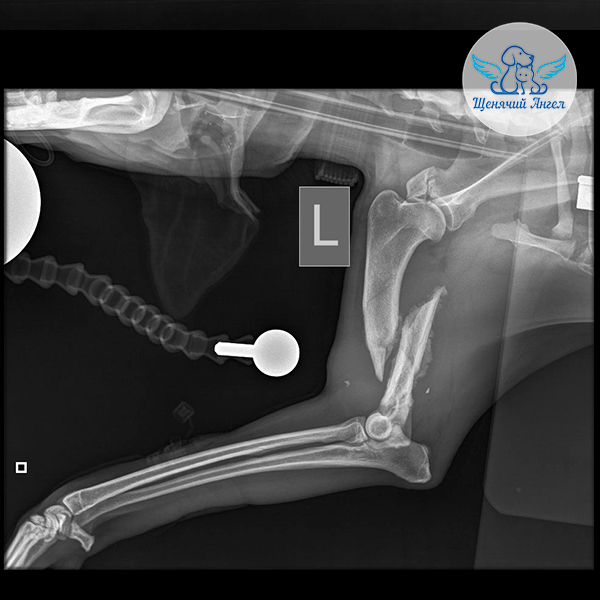

Когда состояние стабилизировалось, мы перевезли Аллочку в Москву на консультацию к хирургу Илье Фёдоровичу Вилковыскому 👨🏻‍⚕️(Ветеринарный центр «МЕДВЕТ»). Рентген выявил комплекс повреждений опорно-двигательного аппарата. На левую переднюю лапу она не может опираться из-за перелома плечевой кости и отрыва надсуставного бугорка лопатки 🥺. Задние лапки также пострадали: справа – вывих тазобедренного сустава, слева – переломы подвздошной, тазовой и лонной костей 😢.

– Левая передняя лапа: необходимо собрать и стабилизировать плечевую кость, чтобы обеспечить правильное сращение.

– Правая задняя лапа: требуется резекционная артропластика – удаление головки и шейки бедренной кости.

– Левая задняя лапа: повреждены структуры таза; врач восстановит положение отломков и уже во время операции определит, потребуется ли резекционная артропластика или реконструкция суставной впадины ☝🏻.